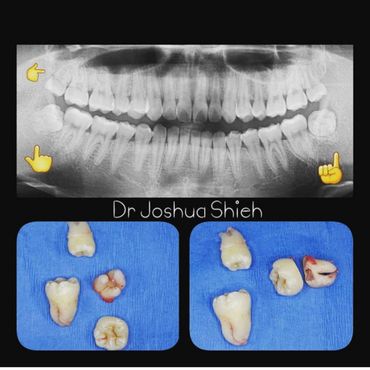

If the tooth is planned for extraction, an x-ray of the area will be taken to plan for the type of extraction.

A surgical extraction is a more complex procedure. It is used if a tooth may have broken off at the gum line or has not come into the mouth yet. Surgical extractions are commonly performed by general dentists or oral surgeons depending on the case. Sometimes it’s necessary to remove some of the bone around the tooth or to cut the tooth in half in order to extract it. For surgical extractions, patients receive local anesthetic. A suture is usually required to control bleeding and facilitate healing.